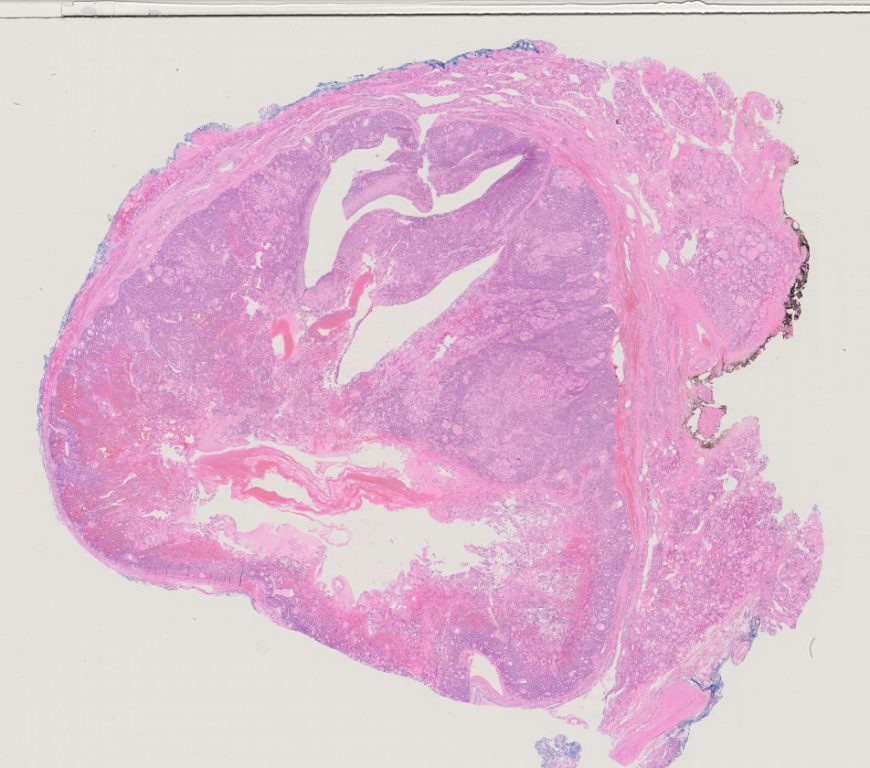

Nikiforov Singapore Study\TST14

TST 014.ndpi

60928

x

53760

20X